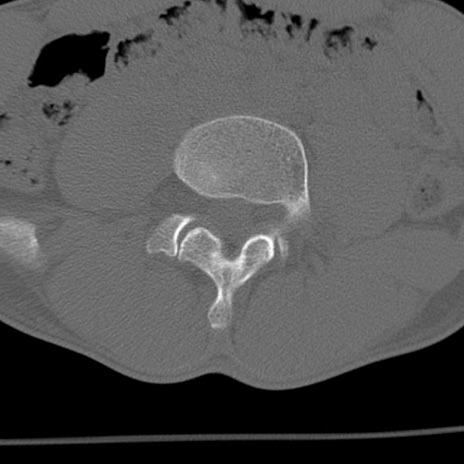

症例3 腰椎CT(横断像)

腰椎CT